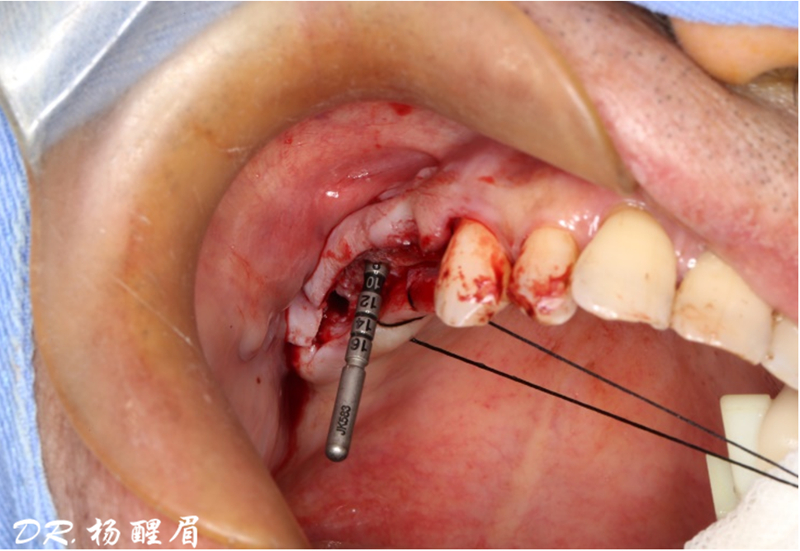

術中操作

®完成標定及配準

®按照術前方案進行備洞及植體植入

®按照術前方案進行備洞及植體植入,醫(yī)生可以通過屏幕軟件引導對手術中植入點、角度、深度實時追蹤

®對植體深度及方向進行確認

®完成3顆植體的植入,植體位點如術前方案設計,均在同軸線。